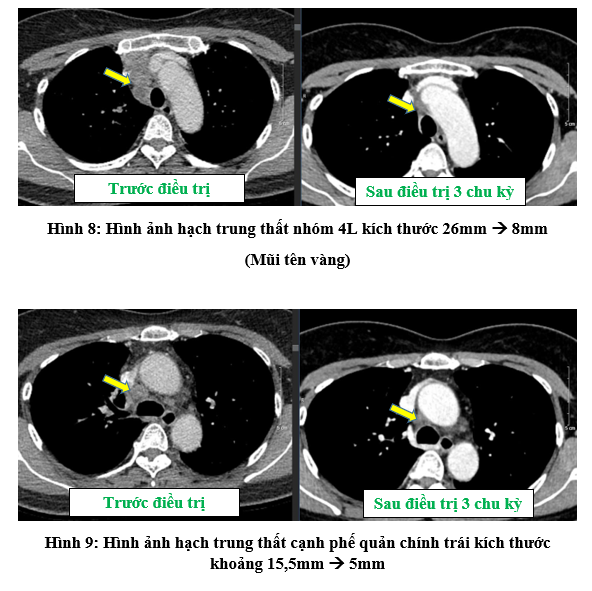

Đánh giá lại sau 3 chu kỳ truyền thuốc miễn dịch kết hợp hóa chất

- Chụt cắt lớp vi tính lồng ngực:

- Chất chỉ điểm khối u sau 3 chu kỳ điều trị đã giảm và trở về bình thường: CEA: 1,29 ng/ml (bình thường: < 4,3 ng/ml);  Cyfra 21-1: 2,28 ng/ml (bình thường: < 2,37 ng/ml).